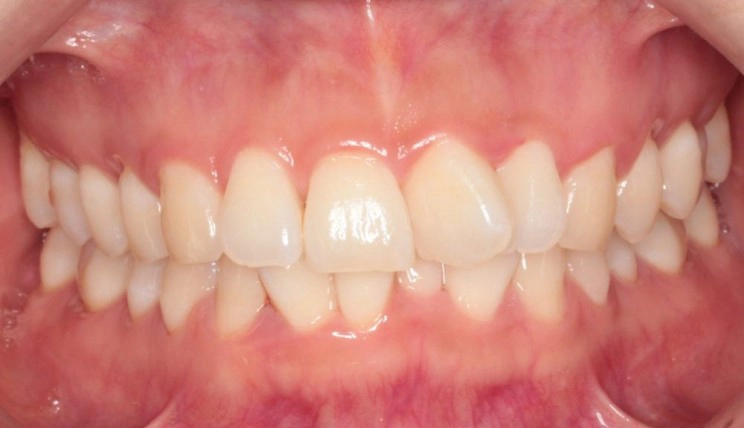

Deep Bite

Deep bite is the condition in which the vertical overlap of anterior teeth in centric occlusion is larger than 30 – 40%.

Patient Information:

Age: 13

Gender: Male

Invisalign Treatment Option: Invisalign Comprehensive

Total Treatment Time:

24 months